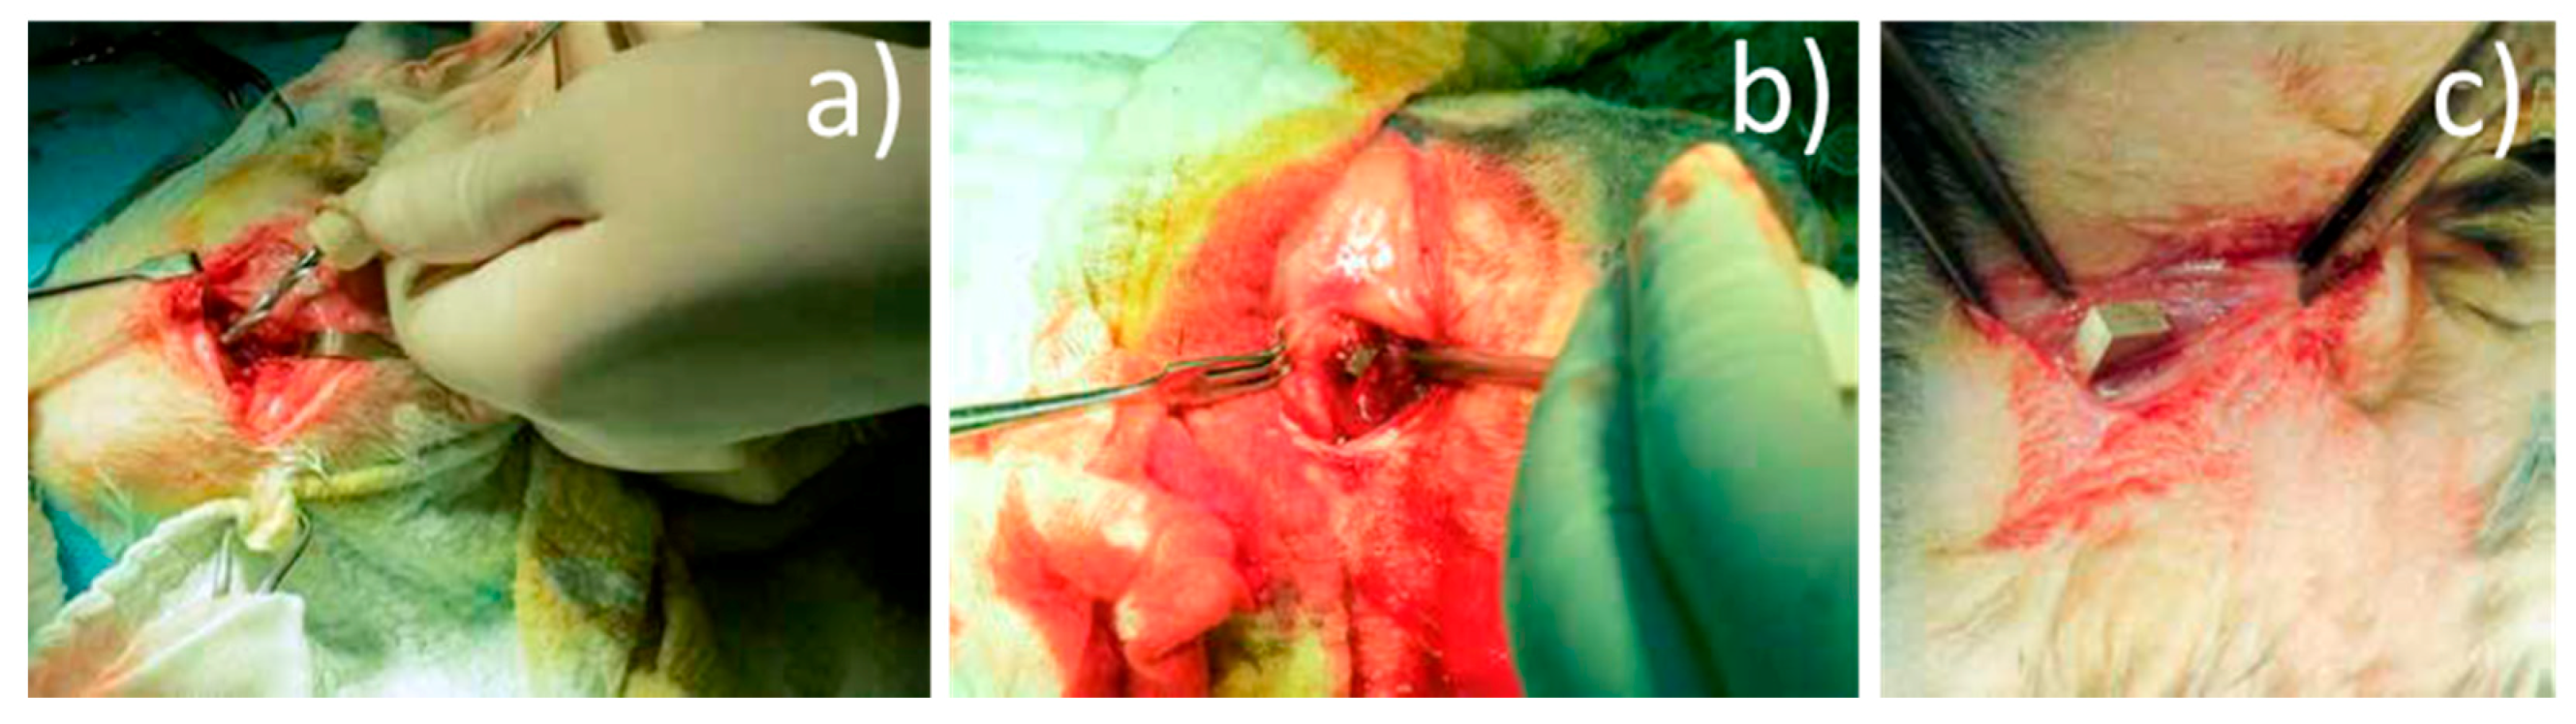

Surgical procedures: The implants were chemically sterilized by ethylene oxide sterilization method, thus avoiding damage to the alloy. The type of anesthesia chosen was veterinary mask inhalation anesthesia, using Sevoflurane. For induction, Ketamine 20 mg/kg C, subcutaneously (SC), was used. Throughout the surgery, we monitored the rabbits’ cardiac activity and respiratory movements. A lateral approach was used at 2 cm, in the 1/3 proximal thigh, centered on the bony relief of the greater femoral trochanter. The lateral cortex was drilled at the base of the greater trochanter using a 3.2 mm diameter drill, in the femoral neck direction (Figure 4a). In the created orifice, the implant was inserted by hammering (Figure 4b). By lateral approach (longitudinal, 3 cm long, middle third thigh), the intersection between the vastus lateralis muscle and the intermediate vastus muscle (anterior head) was identified, and in this space an Mg-1Ca alloy implant was introduced (Figure 4c).

Figure 4.

Surgical procedure: (a) drill hole, (b) implant bone insertion, (c) muscle insertion.